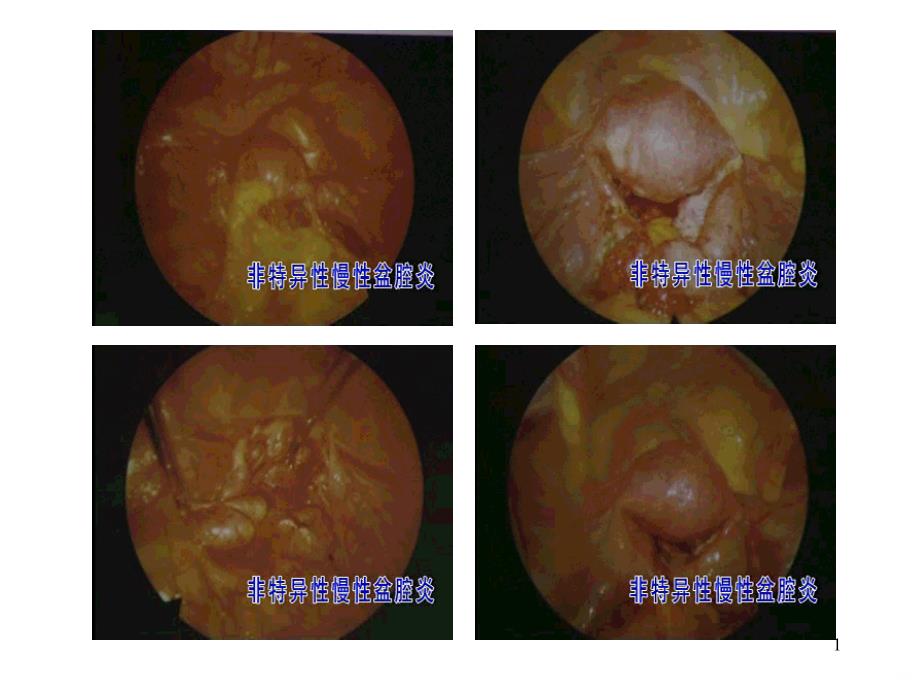

单击此处编辑母版标题样式,单击此处编辑母版文本样式,第二级,第三级,第四级,第五级,,,*,单击此处编辑母版标题样式,单击此处编辑母版文本样式,第二级,第三级,第四级,第五级,*,,*,单击此处编辑母版标题样式,单击此处编辑母版文本样式,第二级,第三级,第四级,第五级,*,,*,,,1,1,附件盆腔脓肿,,,2,附件盆腔脓肿2,,,3,3,宫颈结核,,,4,宫颈结核4,宫颈口充血、脓液流出,,,5,宫颈口充血、脓液流出5,急性盆腔腹膜炎,,,6,急性盆腔腹膜炎6,急性盆腔结缔组织炎,,,7,急性盆腔结缔组织炎7,急性输卵管炎,,,8,急性输卵管炎8,,,9,9,沿上生殖道上行蔓延,,,10,沿上生殖道上行蔓延10,,,11,11,卵巢结核,,,12,卵巢结核12,,,13,13,,,14,14,2024/8/29,,15,2023/9/415,,,16,16,盆腔结核,,,17,盆腔,,,18,18,输卵管充血、水肿、增粗、伞端闭锁,,,19,输卵管充血、水肿、增粗、伞端闭锁19,输卵管积脓,,,20,输卵管积脓20,输卵管结核,,,21,,输卵管卵巢囊肿,,,22,输卵管卵巢囊肿22,输卵管腔内干酪样坏死灶,,,23,输卵管腔内干酪样坏死灶23,,,24,24,,,25,25,,,26,26,子宫肌炎,,,27,子宫肌炎27,,,28,28,2024/8/29,,29,2023/9/429,。